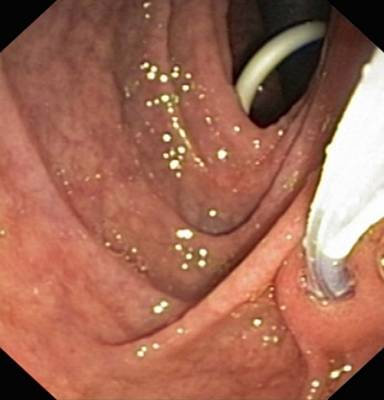

Two months later he had intermittent abdominal pain relieved with analgesics and 4 months later, he presented with severe pain and fever of 15-day duration. On evaluation he was febrile, with tender upper abdomen and elevated leukocyte count (15,900 mm-3). CECT abdomen and EUS revealed a 9x8 cm well defined collection anterior to body and tail of pancreas as well as extending into the lesser sac (Figure 2). Rest of the visualized pancreas had no calcifications, ductal dilatation or any other features of chronic pancreatitis. In view of persistent pain, fever and elevated leukocyte count, a possibility of infected pseudocyst associated with acute pancreatitis was considered and endoscopic cystogastrostomy was done. During the procedure nodularity, grooving and scalloping of duodenal folds was observed (Figure 3) which on histology showed subtotal villous atrophy (Figure 4). IgA anti-tissue transglutaminase levels (Anti tTG, Celekey Germany, ELISA; reference range: 0-15 U/mL) were ordered and were found to be elevated (>300 U/mL). A diagnosis of celiac disease was made and he was started on gluten free diet. Four weeks later he underwent endoscopic retrograde pancreatography which showed evidence of disruption in the tail region. Pancreatic sphincterotomy was done and a 5 Fr x 12 cm pancreatic stent placement. Two months later the stent was removed and a subsequent ultrasound abdomen showed no recurrence of pseudocyst. He has remained well for the last 6 months with no recurrence of abdominal pain.

Figure 3. Endoscopic image from second part of the duodenum showing grooving and nodularity in the duodenum. Pancreatic duct cannulation with sphincterotome and pigtail of the stent placed for cystogastrostomy are also visualized in the picture. |